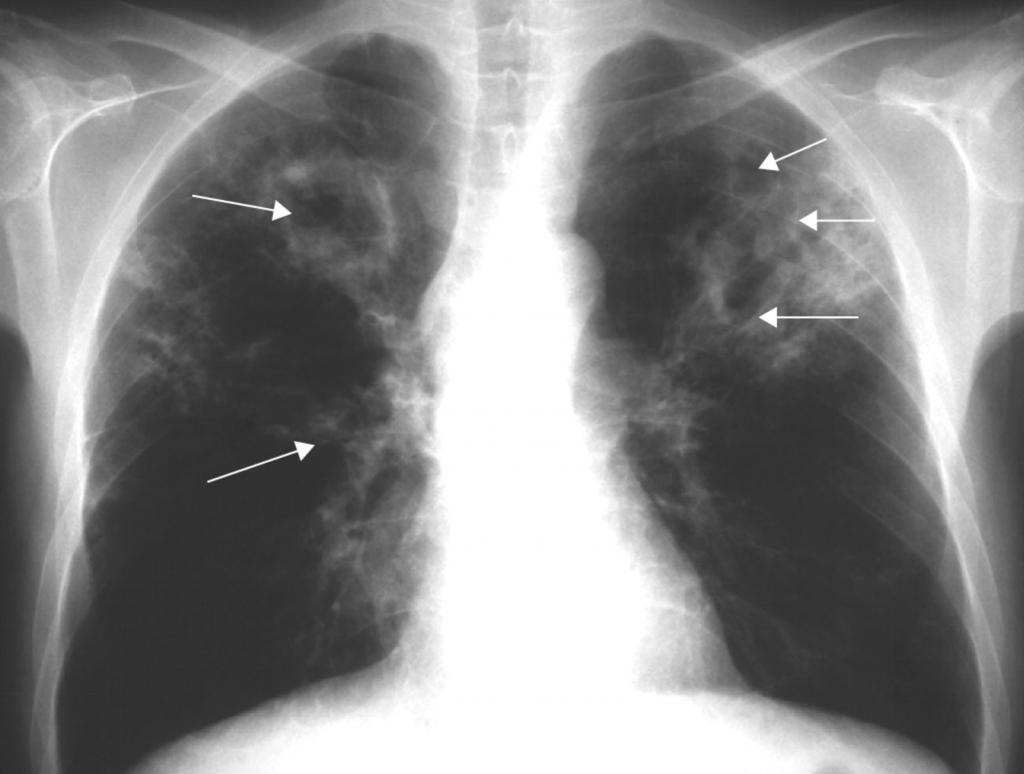

Диссеминированная форма

Эту форму туберкулеза можно поделить на острую, подострую и хроническую. Как правило, развивается остро со стремительным распространением туберкулезных палочек по всему организму.

Выделяют еще одну классификацию в зависимости от способа распространения микобактерий:

• гематогенное — на рентгене проявляется более крупным размеров очагов, находящихся в верхних отделах легких;

• лимфогенное — очаги среднего размера, размещенные преимущественно в нижних отделах;

• лимфобронхогенное — характерно одностороннее поражение в нижних отделах легкого.

То, как выглядит туберкулез на снимке, зависит как от характера его распространения, так и от остроты процесса. Наиболее характерный подтип диссеминированного туберкулеза — милиарный туберкулез. Он представляет собой острую, чаще всего гематогенную инфекцию.

Ниже перечислены основные его признаки на рентгене:

• большое количество мелких очагов, несколько миллиметров в диаметре;

• очаги равномерно распространены по всему легочному полю;

• иногда очаги сливаются;

• корни легких несколько приподняты;

• иногда объем легочной ткани становится меньше.